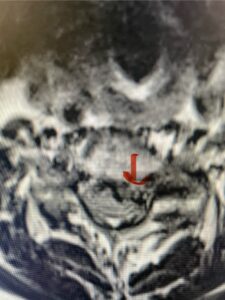

In this next case, this patient is a 47 year-old female who presents with intractable low back pain with severe pain, numbness, and weakness in the right lower extremity that had gotten progressively worse over a year. The patient had failed conservative management including physical therapy and epidurals. She was noted to have ⅘ weakness of plantar flexion. MRI demonstrated a large right L5-S1 disc herniation with severe compression of the descending right S1 nerve root (Fig 3). It was decided to perform a right L5-S1 hemilaminectomy for removal of the disc fragment and decompress the S1 nerve root. When you expose the disc, one must be certain to release any anterior adhesions to the nerve root in order to prevent a dural tear during retraction of the nerve root. It is also important to make sure during exposure and you finally encounter the dura after removing the ligamentum and fat, to make sure you are looking at the nerve root and not the main trunk of the thecal sac because if you don’t you can avulse or damage the nerve root if you retract the wrong structure.

Fig. 3a: Sagittal and axial T2-weighted lumbar MRI images demonstrating large right L5-S1 disc herniation (red arrows)

Fig. 3b

We found a massive subligamentous herniation which had to be revealed by having your partner retract the freed nerve root with a nerve root retractor and putting slight downward pressure on the more medial and anterior disc space. There is nothing more satisfying when the jelly (disc fragment) of the annulus (donut) comes squirting out and you remove a large chunk of disc material that clearly was stretching the ligament membrane and compressing the nerve root. This does cause back pain in addition to radiculopathy not only by the component of mechanical compression but also the stretching of the nerves within the ligament. We performed this surgery and noted that the nerve root was a very angry red color or hyperemic and we removed a large subligamentous fragment. The patient had improvement of her preoperative radicular symptoms.